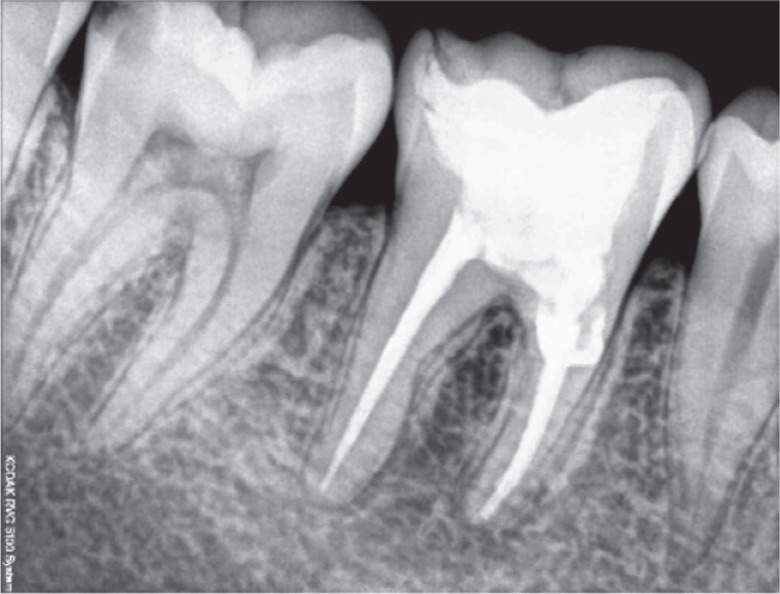

Based on the clinical and radiographic findings, a treatment plan was made. Endodontic therapy was initiated (

Figure 3). Following the cleaning and shaping of the canals, calcium hydroxide (Avue Cal, Dental Avenue, Param Enterprises, Pune, India) was placed as an intracanal medicament for one and half months. The dressing was changed every two weeks. Once the tooth demonstrated signs of radiographic healing of the periapical lesion and the absence of symptoms, the obturation was completed with cold lateral condensation and resin-based sealer (AH Plus, Dentsply DeTrey, Konstanz, Germany,

Figure 3Working length determination radiograph.

Figure 4Master cone length radiograph.